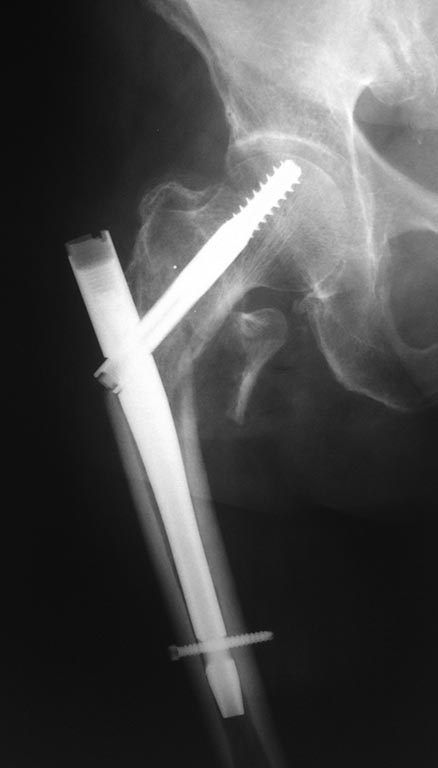

Коллеги, добрый день, прошу помочь в тактике лечения пациента!Пациентка В., 75 лет, без выраженной коморбидности, получила травму в августе 2014 года, диагностирован "Закрытый чрезвертельный перелом правой бедренной кости со смещением отломков", была прооперирована, выполнена закрытая репозиция, интрамедуллярный остеосинтез правой бедренной кости проксимальным бедренным штифтом. К сожалению, первичных снимков не предоставлено, имеются 2 снимка, через 1 месяц после операции, в сентябре 2014 и второй снимок, в январе 2015, пациентка на данный момент передвигается с помощью ходунков, отмечает болезненность при движениях и пальпации, объясняет - "Как-будто кость упирается в железку". Не хочется говорить о неправильной техники и cut-out и/или cut-through синдроме, интересно - что можно сделать и какую тактику лечения выбрать. Заранее благодарен.

Пока нет большой дыры в головке и впадине, надо сделать реостеосинтез. Аналогичный гвоздик, но уже в правильном положении. С остеотомией или без. Надо вторую проекцию хотя бы, а лучше бы еще и КТ.

Все-таки речь тут идет скорее о чрезподвертельном переломе, а не чрезвертельном. И не столько о неправильном введении винта, сколько о неправильном введении самого гвоздя непосредственно в дистальный отломок или его миграции через продольную линию перелома. Конечно нужна КТ. И, вероятно, длинная версия интрамедуллярного фиксатора.

Сделайте боковую проекцию, возможно отсутствует репозиция в передне-заднем направлении. Нередко бывает, что центральный фрагмент разворачивается кзади и шеечный винт мог быть введён в шейку и головку спереди назад ( при отсутствии контроля боковой проекции во время операции)

Снимок плохого качества, правда